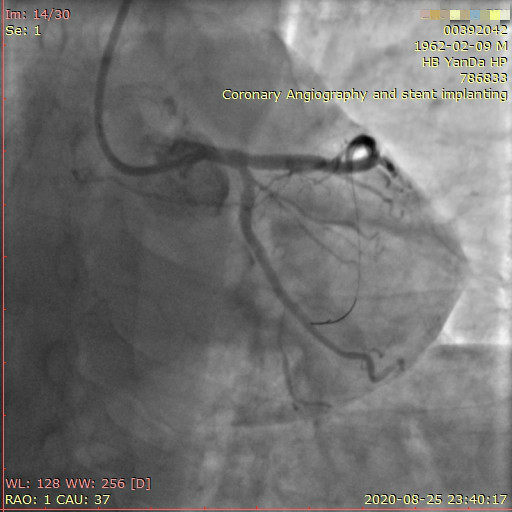

李先生右冠術前影像

李先生右冠術后影像

術前,翟光耀主任還親自為李先生復查冠狀動脈造影,造影結果顯示:患者的前降支、回旋支、右冠等冠脈三支嚴重病變、嚴重鈣化,且均為彌漫性長病變,最重處99%以上管腔極嚴重狹窄。翟主任仔細閱讀造影結果后指出:結合李先生的實際情況,雖然微創介入手術難度比較大,但仍可行;李先生心臟三支主干動脈均存在極其嚴重的狹窄,每一支動脈均至少植入2-3枚支架,根據患者的耐受情況,李先生可能需要分3次分別對三支動脈進行介入手術;考慮到李先生路途遙遠,病情嚴重,不宜反復奔波,并且患者迫切要求能夠徹 底解決病痛,在病情允許的情況下,如果手術順利,爭取為患者進行“一站式”手術,一 次 性解決全部三支動脈病變!

手術方案確定之后,在心血管內三科趙景新主任、介入醫學科富孝晨主任的配合下,翟光耀主任親自擔任主刀,分別依次對李先生的三支動脈進行了完全血運重建。由于手術進展順利,李先生術中沒有任何癥狀,耐受良好,于是成功的將三支動脈“一站式”治療!術中,由于李先生左主干遠端分叉處存在嚴重病變,翟光耀主任選擇國際指南推薦的DK-mini-Crush技術,確保了分叉處兩支主干開口均萬無一失。據悉,DK-mini-Crush技術是目前冠脈分叉病變領域最為復雜及難以掌握的介入技術之一,對手術醫生經驗、體力均提出了極大的挑戰。極為擅長復雜介入技術的翟光耀主任卻用嫻熟的技術確保了李先生手術的成功。

冠狀動脈嚴重鈣化合并狹窄病變是冠脈介入的一大難題,血運重建難度大,成功率低,并發癥發生率高,該例患者的成功救治標志著我院冠脈介入水平又躍上了一個新的臺階。